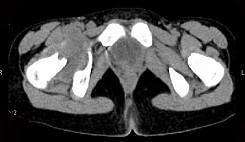

问题 女,11岁,肺部有结核病史,2个月前右髋关节有外伤史,右髋关节部逐渐肿胀疼痛,休息后可减轻,请结合所提供图像,选择最佳选项 ( )

选项 A、右髋关节类风湿关节炎 B、右髋关节痛风 C、化脓性骨关节炎 D、右髋关节退行性变 E、右髋关节结核

答案 E